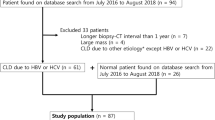

Quantitative texture analysis (QTA) of the liver was performed on abdominal MDCT scans using commercially available software (TexRAD), which uses a filtration-histogram statistic-based technique. Single-slice ROI measurements of the total liver, Couinaud segments IV-VIII, and segments I–III were obtained. CTTA parameters were correlated against fibrosis stage (F0–F4), with biopsy performed within one year for all cases with intermediate fibrosis (F1–F3).

The study cohort consisted of 289 adults (158M/131W; mean age, 51 years), including healthy controls (F0, n = 77), and patients with increasing stages of fibrosis (F1, n = 42; F2 n = 37; F3 n = 53; F4 n = 80). Mean gray-level intensity increased with fibrosis stage, demonstrating an ROC AUC of 0.78 at medium filtration for F0 vs F1-4, with sensitivity and specificity of 74% and 74% at cutoff 0.18. For significant fibrosis (≥F2), mean showed AUCs ranging from 0.71–0.73 across medium- and coarse- filtered textures with sensitivity and specificity of 71% and 68% at cutoff of 0.3, with similar performance also observed for advanced fibrosis (≥F3). Entropy showed a similar trend. Conversely, kurtosis and skewness decreased with increasing fibrosis, particularly in cirrhotic patients. For cirrhosis (≥F4), kurtosis and skewness showed AUCs of 0.86 and 0.87, respectively, at coarse-filtered scale, with skewness showing a sensitivity and specificity of 84% and 75% at cutoff of 1.3.